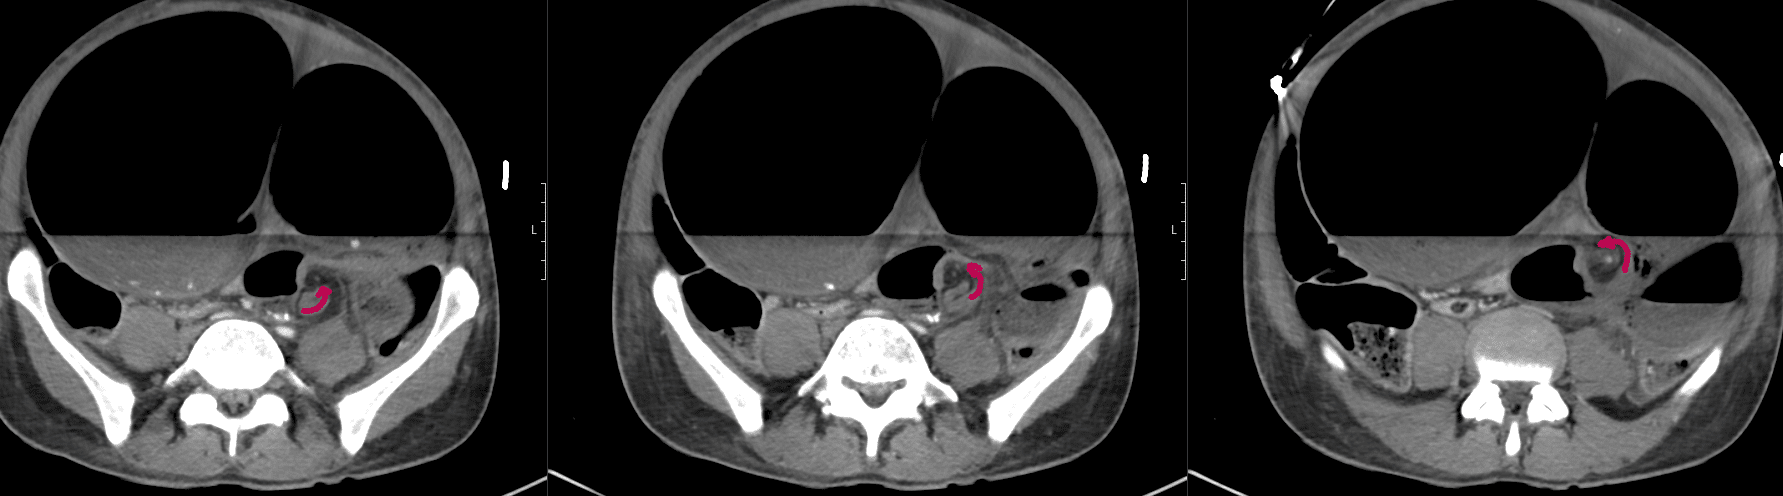

CT mesenteric angiogram

There is evidence of a sigmoid volvulus.

The abdominal aorta as well as the origins of the common iliac arteries and external iliac arteries are compressed by dilated bowel loops however remain patent and there is satisfactory flow distally to the common femoral and superficial femoral arteries.

Comment: Acute sigmoid volvulus with severe bowel obstruction. The dilated bowel loops are significantly compressing the abdominal aorta and pelvic arteries as above. Urgent surgical review recommended.